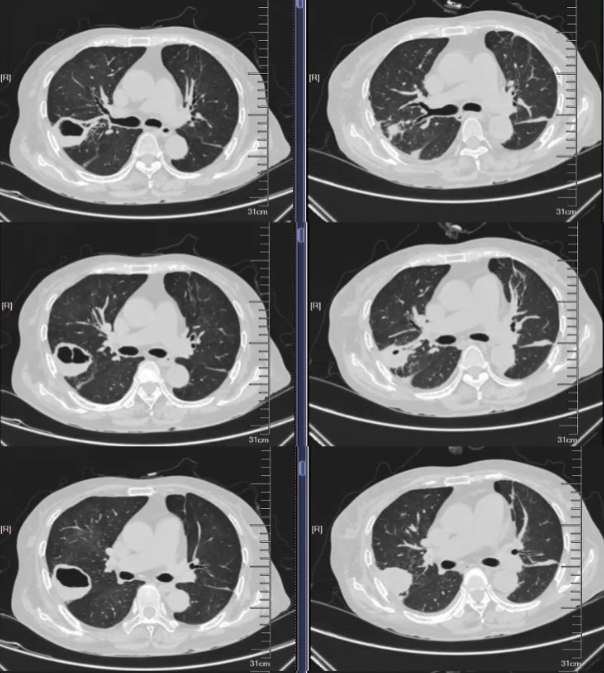

- 胸部CT(图1)(2025-8-15):1、右肺上叶后段空洞性病变(壁厚薄不均,长径约4.9cm,边界尚清,部分边缘稍欠毛糙),双肺多发结节(多发实性、磨玻璃密度结节影,界清,最大者位于右肺下叶背段,长径约1cm,内见空洞),建议CT增强进一步检查。 2、双肺散在炎症、纤维灶;双侧部分支气管轻度扩张;右肺上叶肺大泡。 3、心包部分增厚;主动脉、冠脉多发钙化。 4、腰1椎体楔形压缩。 5、所示双肾形态不规则。

图1.胸部CT(2025-8-15)

2025年8月31日,患者进食后出现严重恶心、呕吐等胃肠道反应,伴肝酶升高,经予止吐、护胃、静脉营养支持及保肝治疗后未见好转,考虑为复方磺胺甲噁唑片不良反应,遂将其剂量逐步减量至0.48g bid后患者胃肠道反应减轻。2025年9月1日复查血液指标提示BNP及D-二聚体升高,加用利尿、抗凝等对症治疗;复查胸部CT(见图4)显示右肺上叶空洞性病变及右肺下叶背段结节较2025年8月15日影像明显缩小,提示当前抗感染治疗方案有效。

本例患者经约1周抗毛霉治疗后复查胸部CT,提示肺部病灶较前明显缩小,血沉、CRP等炎症指标亦较前下降,提示初始治疗有效。在患者病情趋于稳定后,将静脉抗真菌治疗转换为口服序贯治疗,可选药物包括艾沙康唑或泊沙康唑。鉴于患者肾小球滤过率偏低,我们于2025年9月15日起选用艾沙康唑进行口服序贯治疗。同时嘱患者积极控制危险因素,逐步减量并最终停用糖皮质激素,严格调控血糖。1个月后复查胸部CT(见图9)显示右肺病灶持续缩小、空洞消失;实验室检查提示白细胞、CRP、血沉、降钙素原及IL-6均恢复至正常范围,G试验转为阴性。目前患者继续定期随访,监测影像学及血液学指标。

图9.胸部CT(25-8-15 vs 25-9-1 vs 25-10-13)